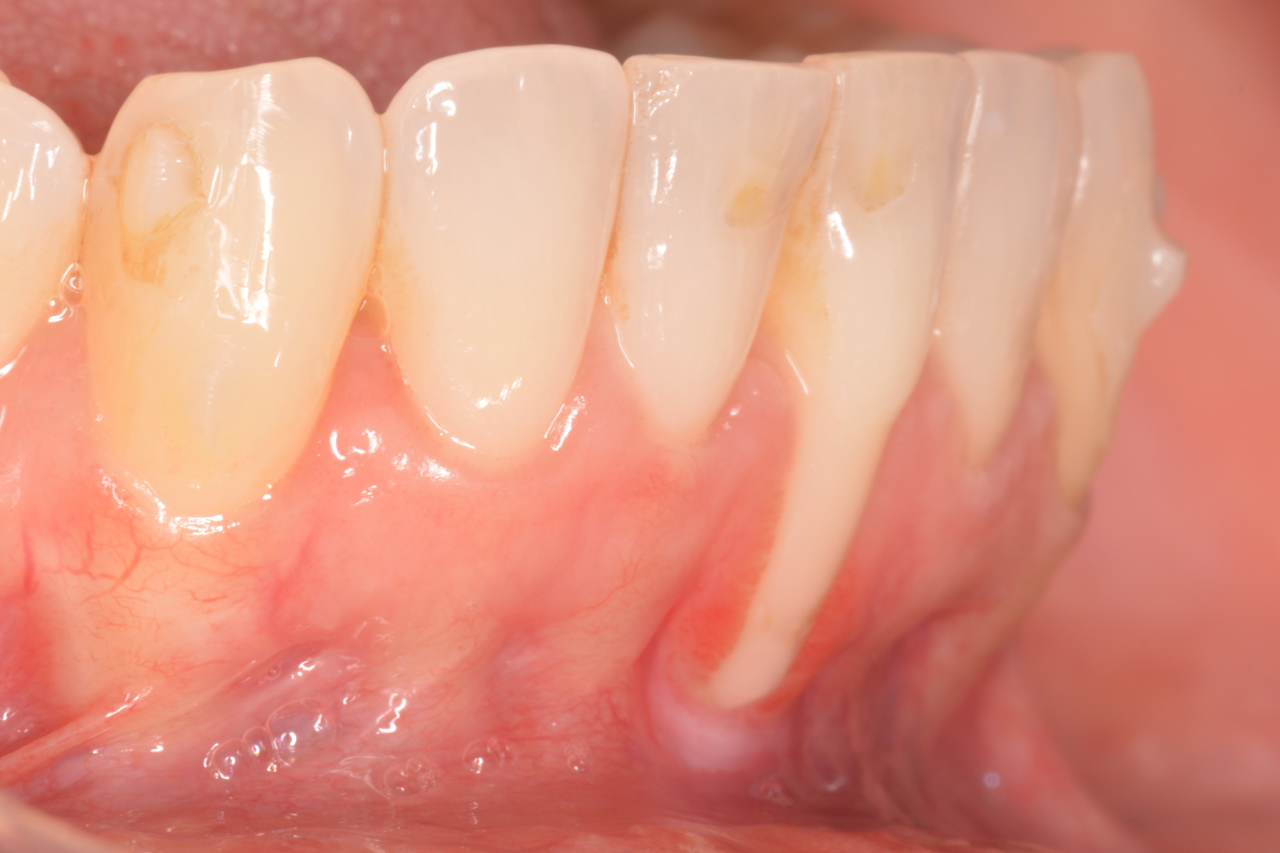

Paciente de 41 años que acude para hacerse un tratamiento de ortodoncia. Tras un incidente durante la ortodoncia una recesion existente en la pieza 31 se agrava.

La sensibilidad del paciente aumenta considerablemente y le molesta tanto el cepillado que impide su correcto mantenimiento.

En este caso se decide realizar una cirugía (injerto de tejido conectivo) durante el tratamiento de ortodoncia y seguir moviendo la raíz hacia una posición más favorable dentro de la arcada. Esto se hizo con la intención de cubrir la exposición de la raíz que le estaba provocando sensibilidad y mejorar la encía resultante de los cuatro incisivos inferiores.